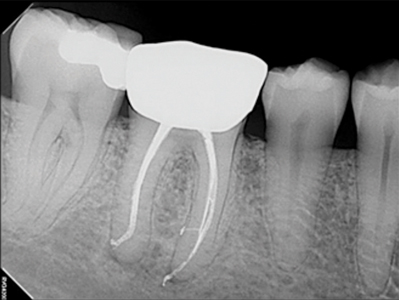

Endodontics became a dental specialty in 1964. At its very beginning, endodontics’ idea of the Triad was revelatory, as was the deep commitment to it. Even in the age before NiTi, microscopes, apex locators, and digital imaging, careful and vigilant attention to technical detail produced verifiable success.3,4 It has been said many times before that we stand on the shoulders of giants, and now future giants stand on our shoulders today. (Fig. 1)

Fig. 1A

Fig. 1B

Fig. 1C

Fig. 1D